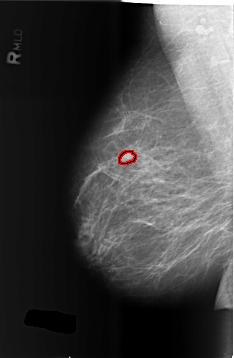

B_3432_1.RIGHT_MLO

RIGHT_MLO LINES 5720 PIXELS_PER_LINE 3736 BITS_PER_PIXEL 12 RESOLUTION 50 OVERLAY

FILE: B_3432_1.RIGHT_MLO.OVERLAY

TOTAL_ABNORMALITIES 1

ABNORMALITY 1

LESION_TYPE MASS SHAPE LOBULATED MARGINS CIRCUMSCRIBED-OBSCURED

ASSESSMENT 4

SUBTLETY 4

PATHOLOGY BENIGN